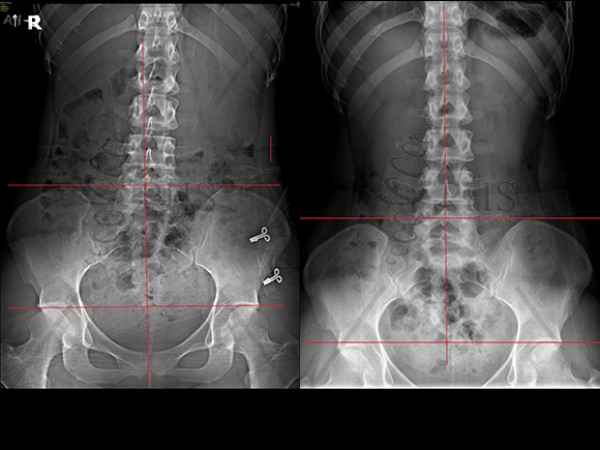

교정사례

PHS효과?